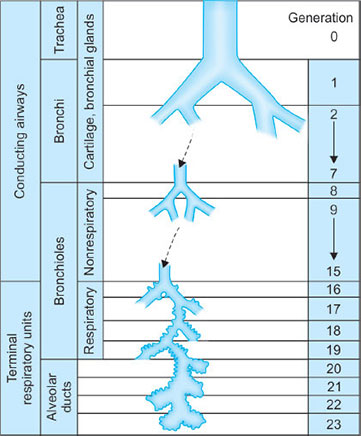

It is lined with columnar ciliated epithelium and divides into the left and right major bronchi at the carina (T4). The bronchi divide 23 times in total (23 generations) (Fig. 16) in order to increase the surface area available for gas exchange. The first 16 generations are termed the conducting zone (no bronchi in his region take part in gas exchange and this forms the anatomical dead space). In an average adult the volume of this space is about 150 mL. From generation 17, small alveoli bud off the bronchi. Generation 17–23 is the respiratory zone where gas exchange occurs. The volume of this zone is about 2–3 liters and there are about 300 million alveoli present within an average lung.